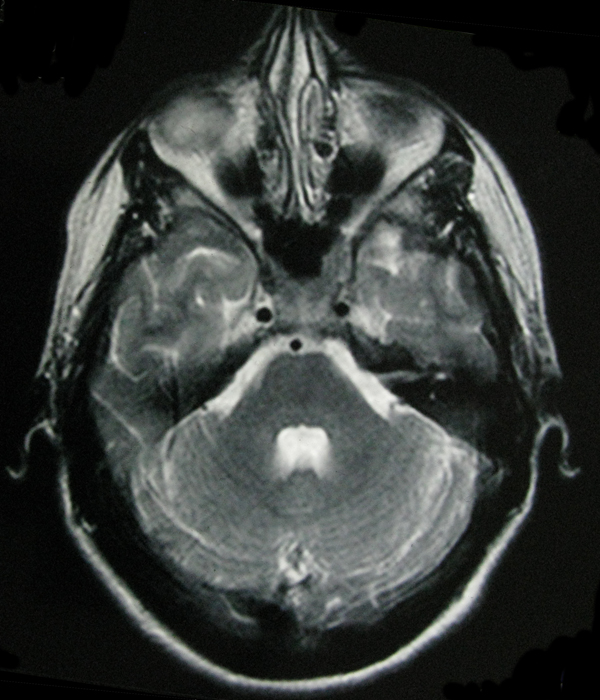

- My Brain in 2009